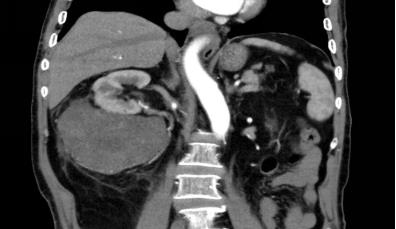

患者黃某, 71歲, “反復(fù)頭暈1年余”到我院內(nèi)科治療。入院常規(guī)腹部彩超發(fā)現(xiàn):雙腎囊腫,雙腎結(jié)石。增強(qiáng)CT診斷提示右腎下后方多發(fā)實(shí)質(zhì)性占位病變,考慮為腹膜后惡性腫瘤(肉瘤可能大)。經(jīng)外二科會(huì)診后,轉(zhuǎn)入外二科治療。

腫瘤CT表現(xiàn)